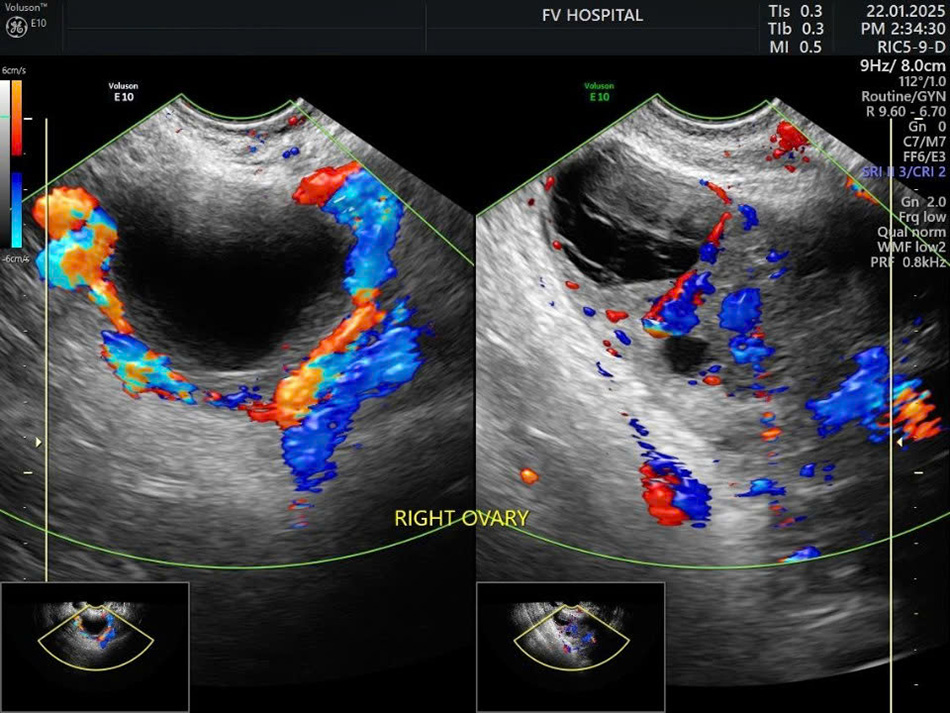

Chị X.A, 30 tuổi, đến Bệnh viện FV với triệu chứng đau nhẹ vùng hố chậu phải. Sau 24 giờ, cơn đau tăng đột ngột, kèm buồn nôn, nôn ói. Siêu âm cho thấy buồng trứng phải phình to gần gấp đôi. ThS.BS Võ Triệu Đạt lập tức yêu cầu hội chẩn liên chuyên khoa với các chuyên gia ngoại khoa và chẩn đoán hình ảnh. Kết luận sau hội chẩn cho thấy đây là tình trạng xoắn phần phụ buồng trứng ở bệnh nhân mang thai 5–6 tuần. ThS.BS Võ Triệu Đạt cho biết: “Xoắn phần phụ buồng trứng ở thai phụ là trường hợp hy hữu, tỷ lệ chỉ 1,6/10.000 thai kỳ”. Những triệu chứng ban đầu gần giống với hàng loạt vấn đề quen thuộc hơn như dọa sảy thai, sinh non, viêm dạ dày… khiến bác sĩ dễ chẩn đoán nhầm. Thực tế, khoảng 57% trường hợp xoắn phần phụ có cơn đau cách hồi khiến việc chẩn đoán bệnh dễ bị nhầm lẫn. Trong khi đó, nếu can thiệp trong 24 giờ đầu, khả năng bảo tồn buồng trứng lên tới 84%. Nếu chẩn đoán muộn, không kịp phẫu thuật để tháo xoắn sẽ nguy hại đến cả mẹ và thai nhi như hoại tử buồng trứng ở người mẹ, ảnh hưởng nghiêm trọng đến hệ thống nội tiết và sinh sản của mẹ trong tương lai, còn thai kì sẽ tăng nguy cơ sẩy thai, doạ sanh non thậm chí thai chết lưu do hậu quả của thiếu máu nuôi.

Hình siêu âm tái khám sau 1 tuần: bên trái buồng trứng xoắn, bên phải buồng trứng đã được tưới máu lại bình thường sau phẫu thuật. (Ảnh: FV)